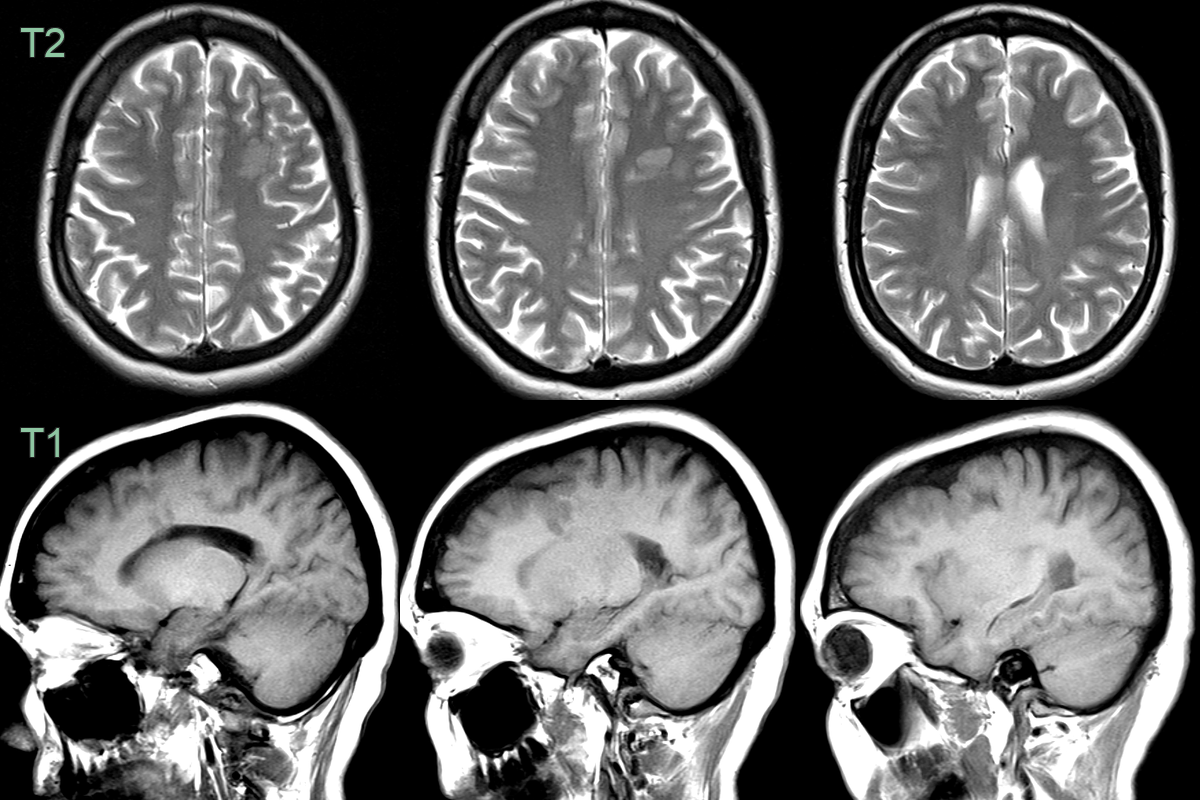

• 16-year-old patient with a life long history of temporal seizures (deja vu and vacant episodes with secondary generalisation).

• MRI showed nodular grey matter heterotopia in the right temporal lobe.

• The right cerebral hemisphere and skull was smaller on the right.